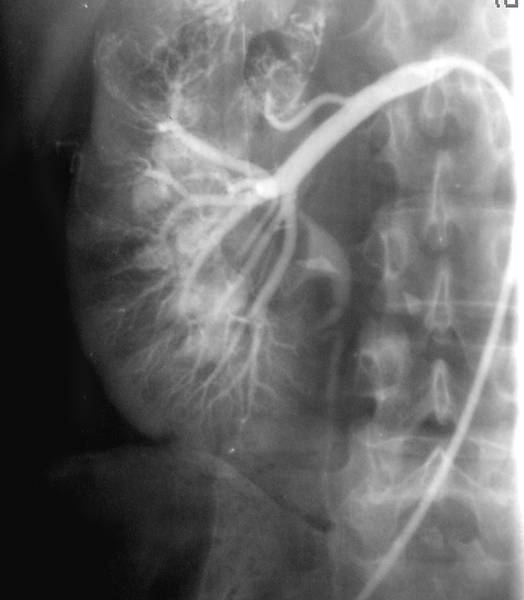

В зависимости от способа введения контрастного вещества различают транслюмбальную и трансфеморальную почечную ангиографию. В первом случае заполнение почечных артерий препаратом осуществляют с помощью пункции аорты со стороны поясницы. В настоящее время транслюмбальную почечную ангиографию не применяют. Трансфеморальную ангиографию выполняют по методу Сельдингера. Для этого пунктируют бедренную артерию и проводят по ней катетер в брюшной отдел аорты до уровня отхождения почечных артерий. Контрастное вещество вводят по катетеру, выполняя, таким образом, аортографию. При этом выполняют серию снимков, изображения на которых позволяют судить о четырёх фазах циркуляции контрастной жидкости в почке и мочевыводящих путях. Первая фаза — артериограмма; контрастное вещество визуализируют в аорте и магистральных артериях (рис.). Вторая фаза — нефрограмма; возникает изображение почечной паренхимы в виде плотной тени. Далее удаётся зафиксировать третью фазу (венограмму), когда происходит отток контрастной жидкости по почечным венам. Четвёртая фаза — экскреторная; мочевыводящие пути наполняются контрастным препаратом.

Селективную почечную артериографию применяют для получения более чёткого изображения интересующей зоны. При этом клюв катетера из аорты вводят в выбранную артерию и контрастируют сосудистое русло (рис. ).

Селективная почечная артериограмма при опухоли правой почки: в верхнем сегменте определяются патологические сосуды; видна комбинация артериальной, нефрографической и экскреторной фаз исследования.